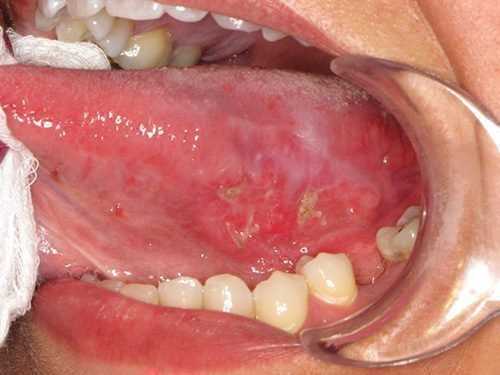

Π’ΡΠ±Π΅ΡΠΊΡΠ»Π΅Π·

Π’ΡΠ±Π΅ΡΠΊΡΠ»Π΅Π·ΠΠΎΡΠ°ΠΆΠ΅Π½ΠΈΠ΅ ΡΠ·ΡΠΊΠ° ΠΏΡΠΈ ΠΌΠΈΠΊΠΎΡΠΈΡΠ΅ΡΠΊΠΎΠΉ ΠΈΠ½ΡΠ΅ΠΊΡΠΈΠΈ Π±ΡΠ²Π°Π΅Ρ ΠΏΠ΅ΡΠ²ΠΈΡΠ½ΡΠΌ ΠΈΠ»ΠΈ Π²ΡΠΎΡΠΈΡΠ½ΡΠΌ Π½Π° ΡΠΎΠ½Π΅ Π·Π°ΠΏΡΡΠ΅Π½Π½ΠΎΠ³ΠΎ ΡΡΠ±Π΅ΡΠΊΡΠ»Π΅Π·Π° Π»Π΅Π³ΠΊΠΈΡ . Π£ Π±ΠΎΠ»ΡΠ½ΡΡ Π½Π°Π±Π»ΡΠ΄Π°Π΅ΡΡΡ ΠΈΠ·ΡΡΠ·Π²Π»Π΅Π½ΠΈΠ΅ ΡΠ·ΡΠΊΠ°, ΡΠ°Π½ΠΊΠΈ ΠΈΠΌΠ΅ΡΡ ΡΠ΅Π»Π΅Π²ΠΈΠ΄Π½ΡΡ ΠΈΠ»ΠΈ ΠΎΠΊΡΡΠ³Π»ΡΡ ΡΠΎΡΠΌΡ Ρ ΡΡΡ Π»ΡΠΌΠΈ ΠΊΡΠ°ΡΠΌΠΈ. Π―Π·Π²ΠΎΡΠΊΠΈ Π±ΠΎΠ»Π΅Π·Π½Π΅Π½Π½Ρ, Π»Π΅Π³ΠΊΠΎ ΠΊΡΠΎΠ²ΠΎΡΠΎΡΠ°Ρ, Π½Π° Π΄Π½Π΅

Π²ΠΈΠ΄Π½Ρ ΡΠ·Π΅Π»ΠΊΠΈ ΡΠ΅ΡΠΎ-ΠΆΠ΅Π»ΡΠΎΠ³ΠΎ ΡΠ²Π΅ΡΠ°.

ΠΠ°ΡΠΎΠ»ΠΎΠ³ΠΈΡΠ΅ΡΠΊΠΈΠ΅ ΠΎΠ±ΡΠ°Π·ΠΎΠ²Π°Π½ΠΈΡ ΠΌΠΎΠ³ΡΡ Π±ΡΡΡ Π΅Π΄ΠΈΠ½ΠΈΡΠ½ΡΠΌΠΈ ΠΈΠ»ΠΈ ΠΌΠ½ΠΎΠΆΠ΅ΡΡΠ²Π΅Π½Π½ΡΠΌΠΈ, Π»ΠΎΠΊΠ°Π»ΠΈΠ·ΠΎΠ²Π°ΡΡΡΡ Π² Π»ΡΠ±ΠΎΠΉ ΡΠ°ΡΡΠΈ ΡΠ·ΡΠΊΠ°, Π½ΠΎ ΡΠ°ΡΠ΅ Π²ΡΠ΅Π³ΠΎ Π²ΡΡΡΠ΅ΡΠ°ΡΡΡΡ Π½Π° ΠΊΠΎΠ½ΡΠΈΠΊΠ΅, ΠΊΠΎΡΠ½Π΅, ΡΠΏΠΈΠ½ΠΊΠ΅ ΠΈΠ»ΠΈ Π±ΠΎΠΊΠΎΠ²ΡΡ ΠΏΠΎΠ²Π΅ΡΡ Π½ΠΎΡΡΡΡ ΠΌΡΡΠ΅ΡΠ½ΠΎΠ³ΠΎ ΠΎΡΠ³Π°Π½Π°. ΠΡΠΈ Π·Π°ΠΏΡΡΠ΅Π½Π½ΠΎΠΌ ΡΠ΅ΡΠ΅Π½ΠΈΠΈ ΡΡΠ±Π΅ΡΠΊΡΠ»Π΅Π·Π° Π½Π° ΠΏΠΎΠ²Π΅ΡΡ Π½ΠΎΡΡΠΈ ΡΠ»ΠΈΠ·ΠΈΡΡΡΡ ΡΠΎΡΠΌΠΈΡΡΡΡΡΡ ΠΌΠ½ΠΎΠΆΠ΅ΡΡΠ²Π΅Π½Π½ΡΠ΅ ΠΌΠΈΠ»ΠΈΠ°ΡΠ½ΡΠ΅ ΡΠ·Π΅Π»ΠΊΠΈ, ΡΠΏΠΎΡΠΎΠ±Π½ΡΠ΅ ΡΠ»ΠΈΠ²Π°ΡΡΡΡ Π² ΠΎΠ±ΡΠΈΡΠ½ΡΠ΅ ΡΠ·Π²Ρ.